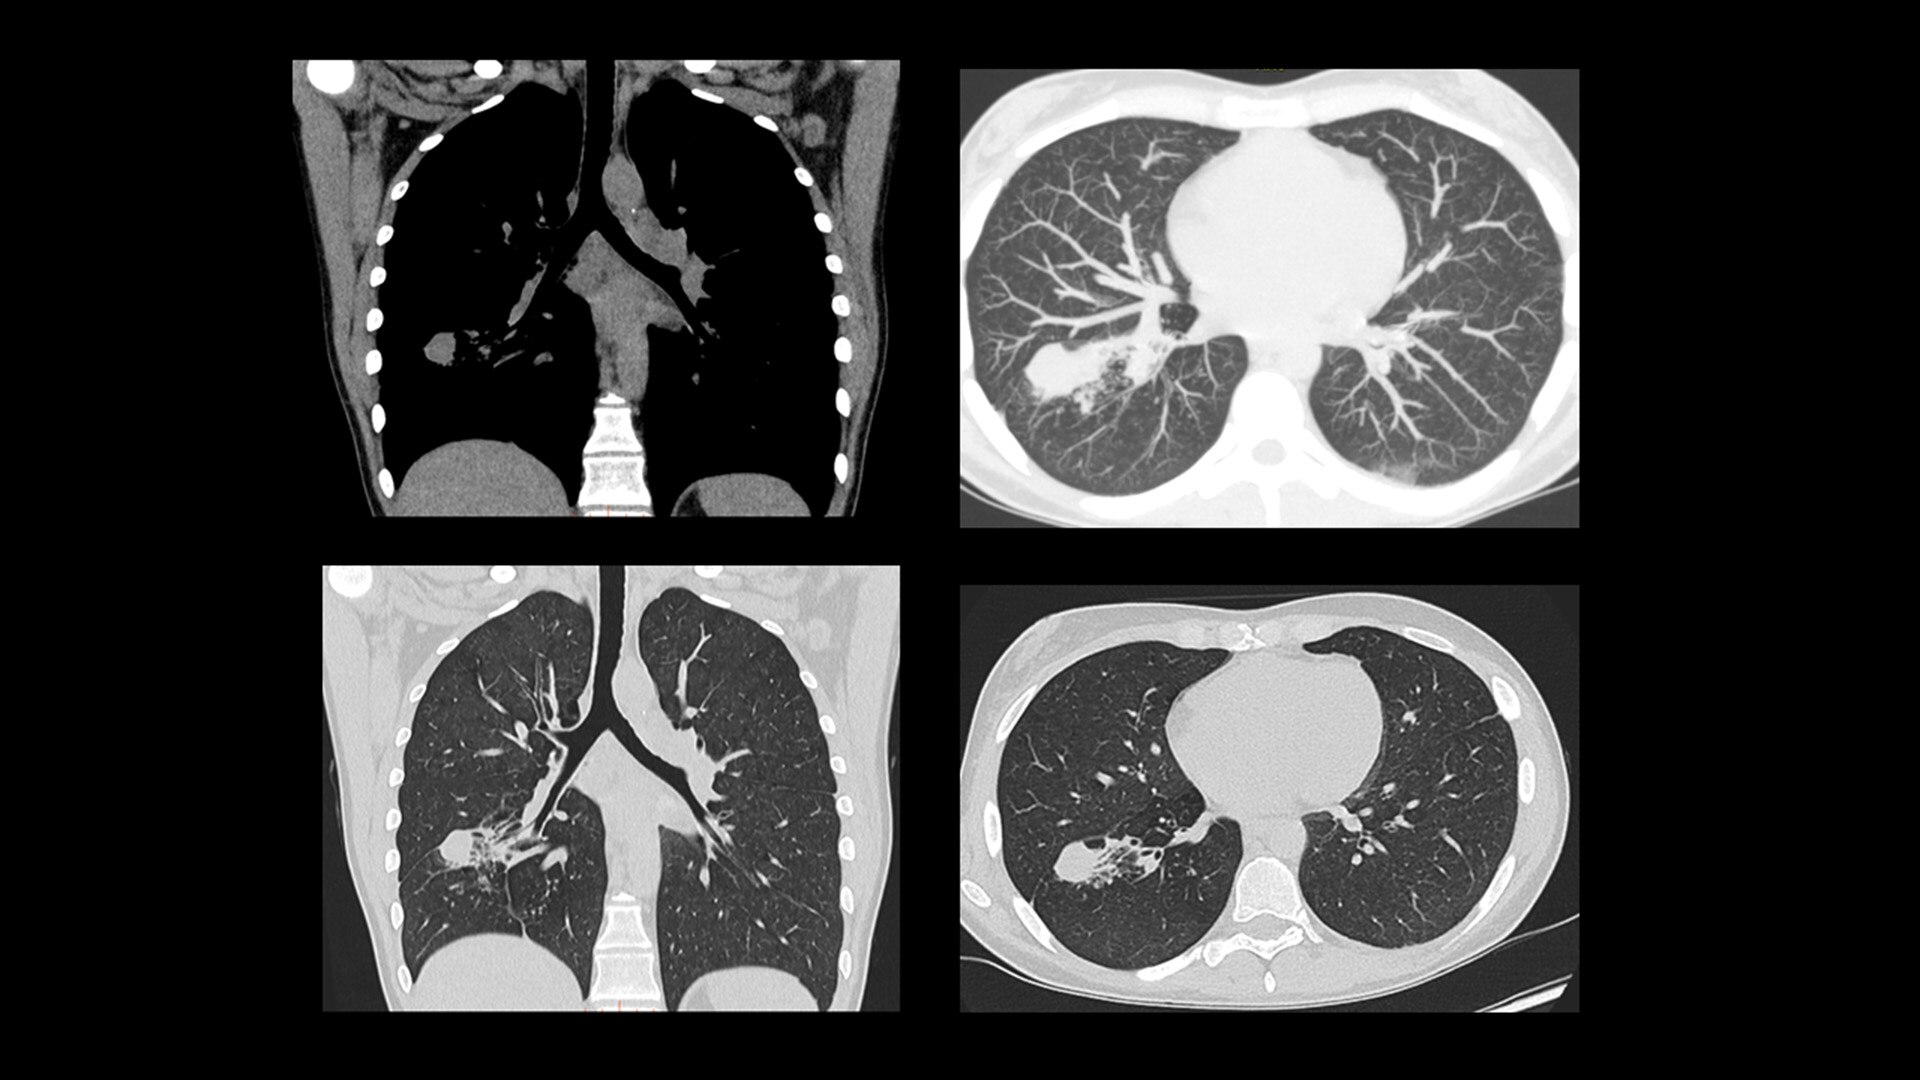

Cardiac CT has become a front-line, non-invasive imaging tool for diagnosing, treatment planning and monitoring of cardiovascular disease

Healthcare providers are striving to improve patient health but are struggling with increasingly complex exams, insufficient or inexperienced staff, and operational and capital efficiency. Revolution™ Vibe, designed to deliver leading-edge technology, features advanced cardiovascular capability. It improves patient access and operational efficiency, prioritizes patient care and supports your facility's growth with lower lifecycle costs.

Unlimited 1-Beat Cardiac is designed to provide consistent, high-quality imaging for accurate diagnoses, even in challenging patients with atrial fibrillation, breath-holding difficulties, heavily calcified coronaries, in-stent restenosis, and situations where an ECG trace is unavailable.